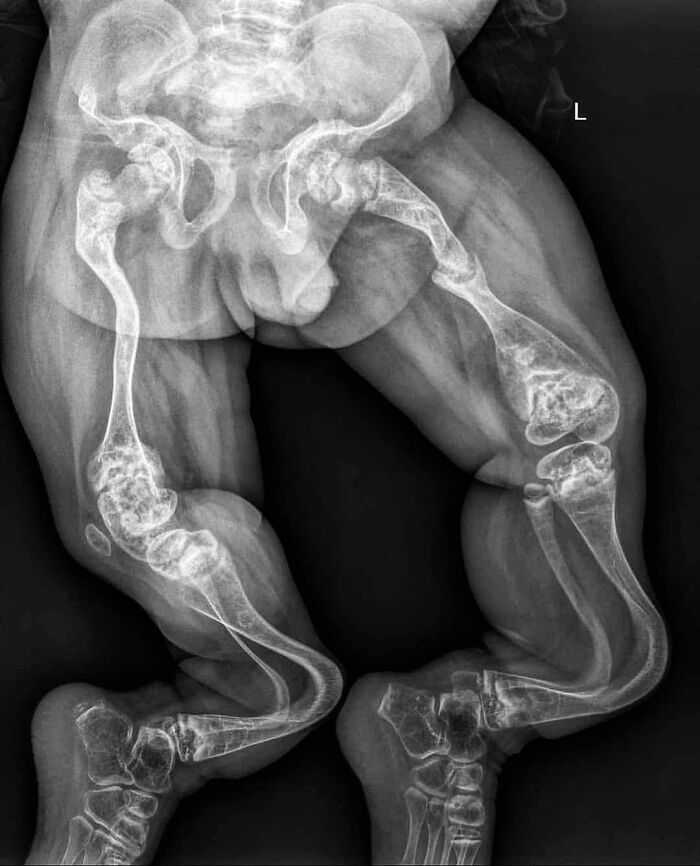

RTG dziecka z osteogenesis imperfecta typu III — postępujące deformacje i kruchość kości